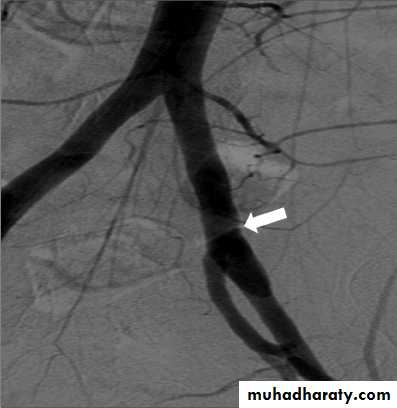

Angiography of partially severed injury